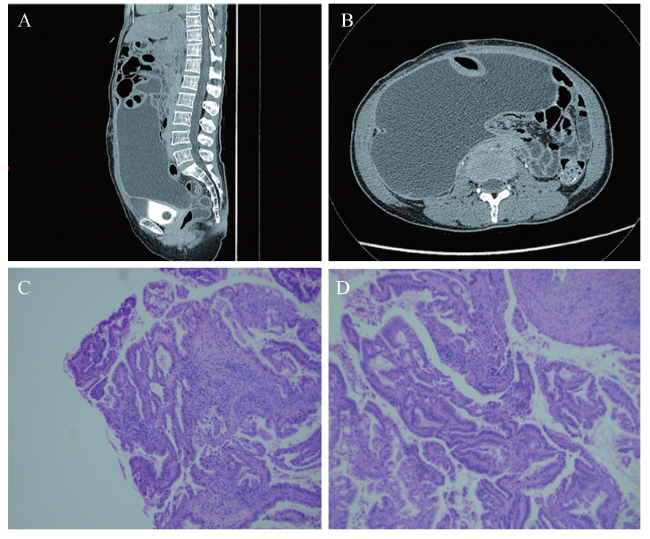

图1 一例卵巢癌淋巴切除术后顽固性淋巴漏的辅助检查结果

A:腹部增强CT(矢状位);B:腹部增强CT(横断位);C、D:病理玻片会诊结果示卵巢交界性子宫内膜样腺癌(HE染色,×200)

病理科:考虑为卵巢交界性子宫内膜样腺癌、伴局灶癌变,见图1C、D。

目前临床常见腹水病因有肿瘤性、肝源性、结核性、胰源性、免疫性、梅格斯综合征及低蛋白血症等。本例患者腹水癌抗原125升高,病理玻片会诊考虑为卵巢交界性子宫内膜样腺癌、伴局灶癌变,但多次综合评估未见肿瘤复发征象,结合手术记录及术后病理,我科评估其为早期肿瘤(ⅠC期),且后续治疗疗程已足,在治疗期间出现病情进展概率极低。患者否认既往肝炎、高血压等内科病史,心、肝、肾功能及结核相关检查未见异常,同时未见胰腺病变征象。患者术前亦无腹水形成,可排除梅格斯综合征可能。回顾患者临床资料,其腹水出现时机为术后1个月,腹水为澄清、淡黄,腹水甘油三酯< 0.1 mmol/L,可排除乳糜漏,但CT提示淋巴囊肿存在,入院时合并腹膜炎。因此,经一系列讨论及病情观察后,考虑为术后淋巴漏合并感染;予诊断性治疗,患者腹水量下降,随访显示患者已无腹胀等不适。